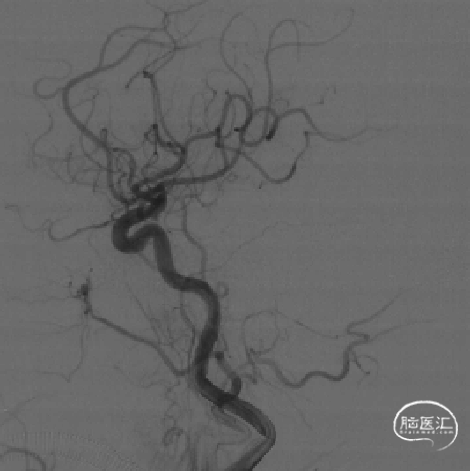

DSA评估:右侧颈内动脉末端闭塞,颈内动脉走行迂曲

DSA评估:前交通开放,左侧颈内动脉通过前交通动脉向右侧大脑前动脉代偿供血,并逆向充盈至右侧大脑前动脉A1段

DSA评估:后循环未见明显向右侧颈内动脉供血区代偿供血

DSA提示右侧颈内动脉末端闭塞,局部可见“杯口”征;左侧颈内动脉通过前交通代偿,并逆向充盈至右侧A1段;该患者为颈内动脉末端“T”型闭塞。结合房颤病史,病因分型为心源性栓塞。

长鞘跟过颈内动脉起始部弯曲段后,在持续负压抽吸下,微导管微导丝顺利辅助抽吸导管通过海绵窦段至闭塞段以远接触血栓(红色箭头所示为导管头端,白色长箭头所示为路图下闭塞段;白色短箭头为长鞘位置)。

不减影图像中长鞘(白色箭头)和抽吸导管(红色箭头)位

侧位:抽吸导管到位、接触抽吸过程。